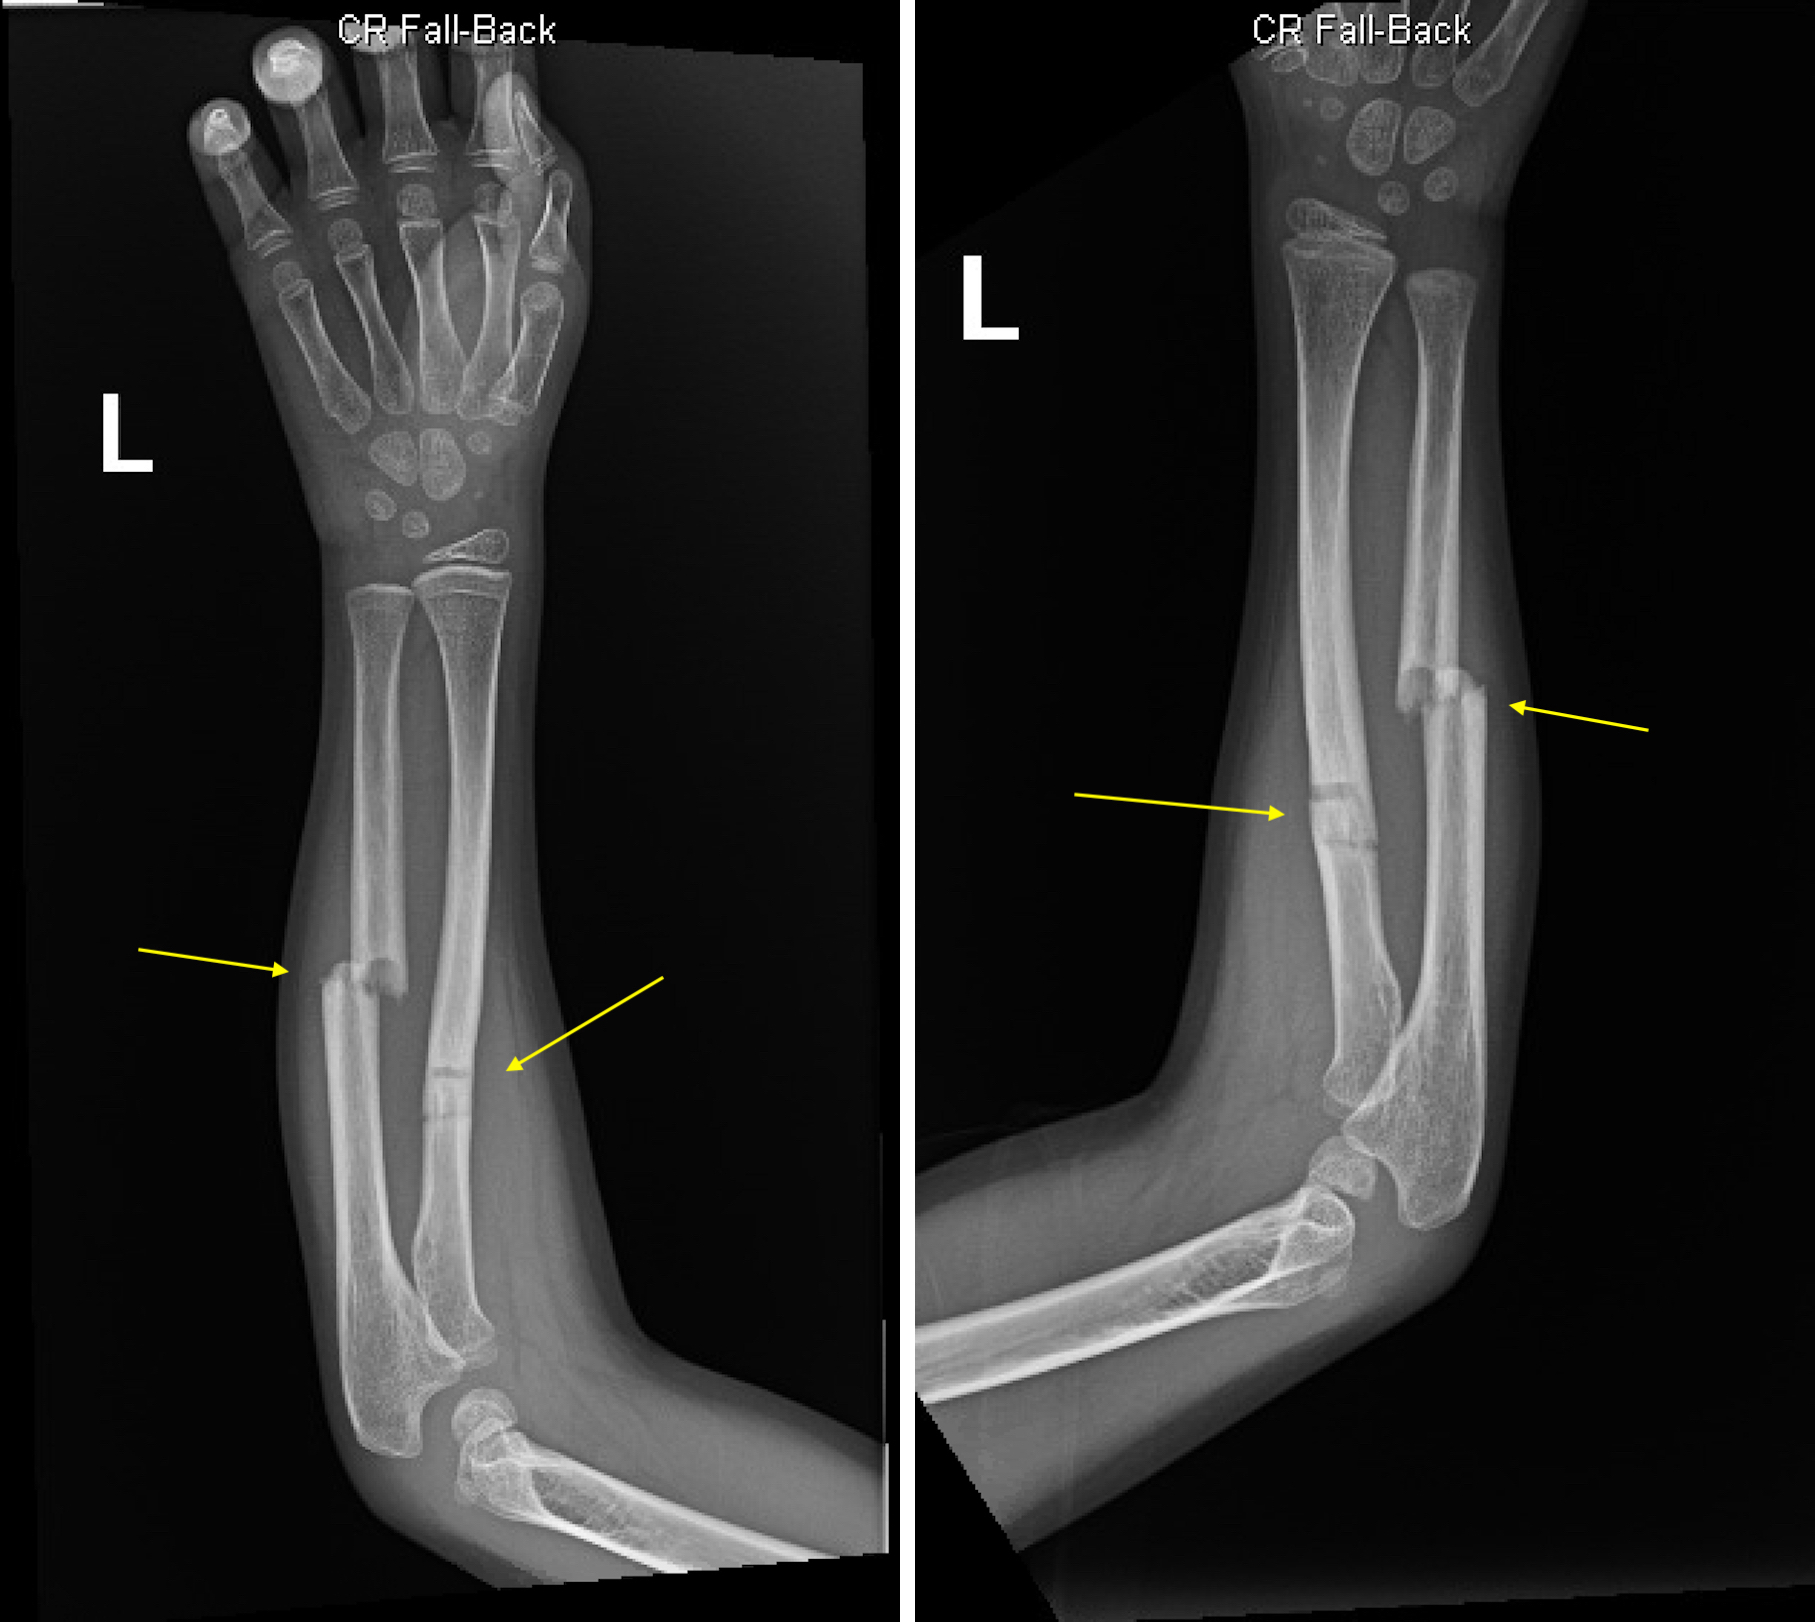

Greenstick Fractures of the mid- Radial and Ulnar Diaphysis with Volar ...

• Greenstick Fracture: The bone bends and cracks, but does not break completely. This type is common in children.

Children and older adults have unique considerations when it comes to fractures and breaks. For children, the bones are still growing, and certain types of fractures, such as greenstick fractures, are more common. Older adults, on the other hand, are at a higher risk of fractures due to conditions like osteoporosis. Special care and treatment plans are often required for these age groups.